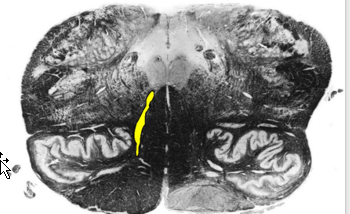

Describe Sensory Decussation of the Dorsal Columns:

Pathway? Locations?

What are the names of the fibers decussating?

Sensory Decussation of Dorsal Column

Dorsal Columns → ascend to caudal medulla → synapse @ gracile/cuneate nucleus

Location: deep to gracile tubercle (clava) and cuneate tubercle

dorsal column nuclei → Decussates @ tegmentum → medial lemniscus → ascend to thalamus (VPL).

Fibers Decussating = internal arcuate fibers

Fibers ascending in medial lemniscus = somatotopically organized